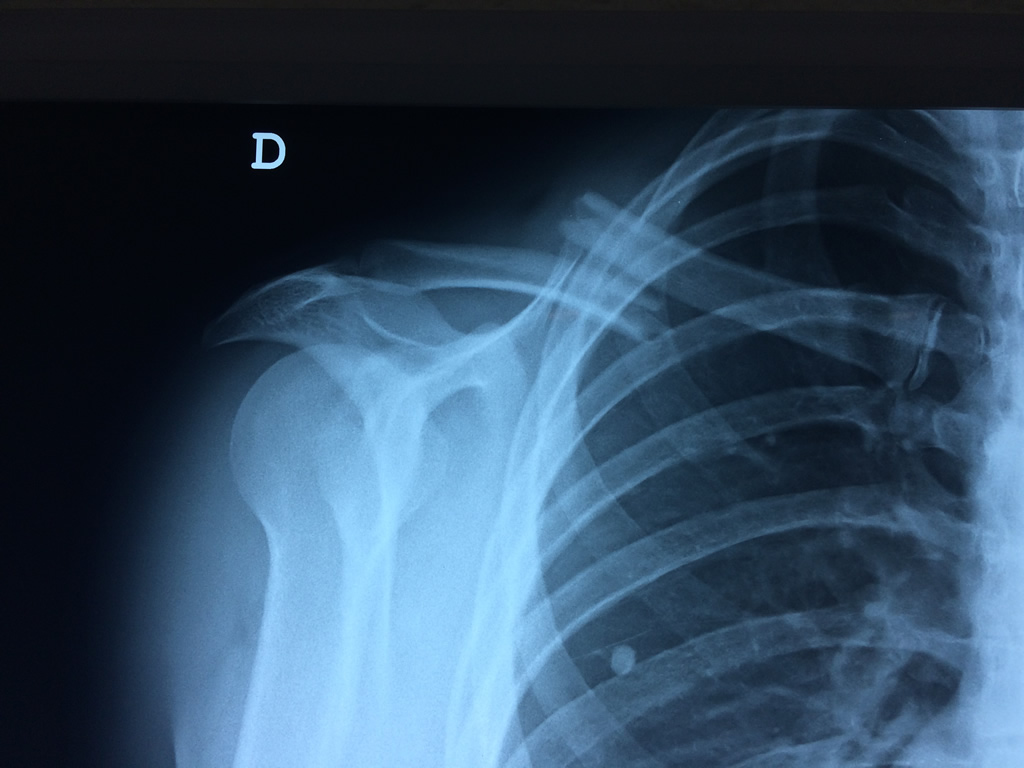

Cirugías de Húmero - Clavícula

La clavícula es un hueso largo, con forma de "S" itálica, situado en la parte anterosuperior del tórax. Junto con la escápula forman la cintura escapular. Se puede palpar por toda su longitud y se extiende del esternón al acromion de la escápula, siguiendo una dirección oblicua lateral y posterior.